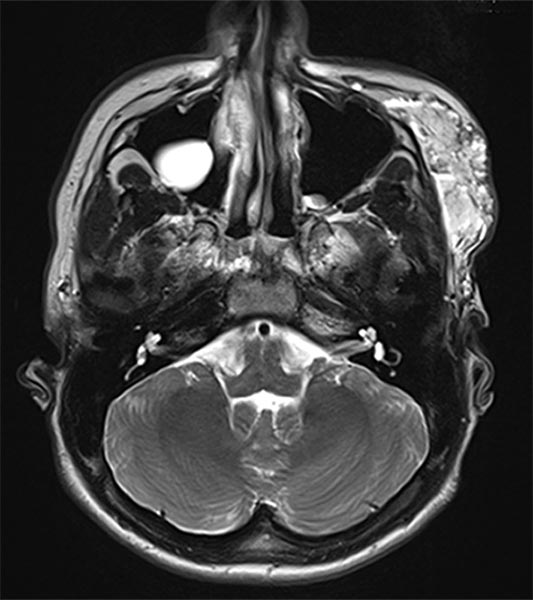

Axial, T2-weighted fat-suppressed MRI of the face. The venous malformation appears typically very hyperintense here too. No expansion into the depth.

Axial, T2-weighted MRI of the face (without fat suppression). The venous malformation is highly hyperintense and shows fluid-fluid levels.